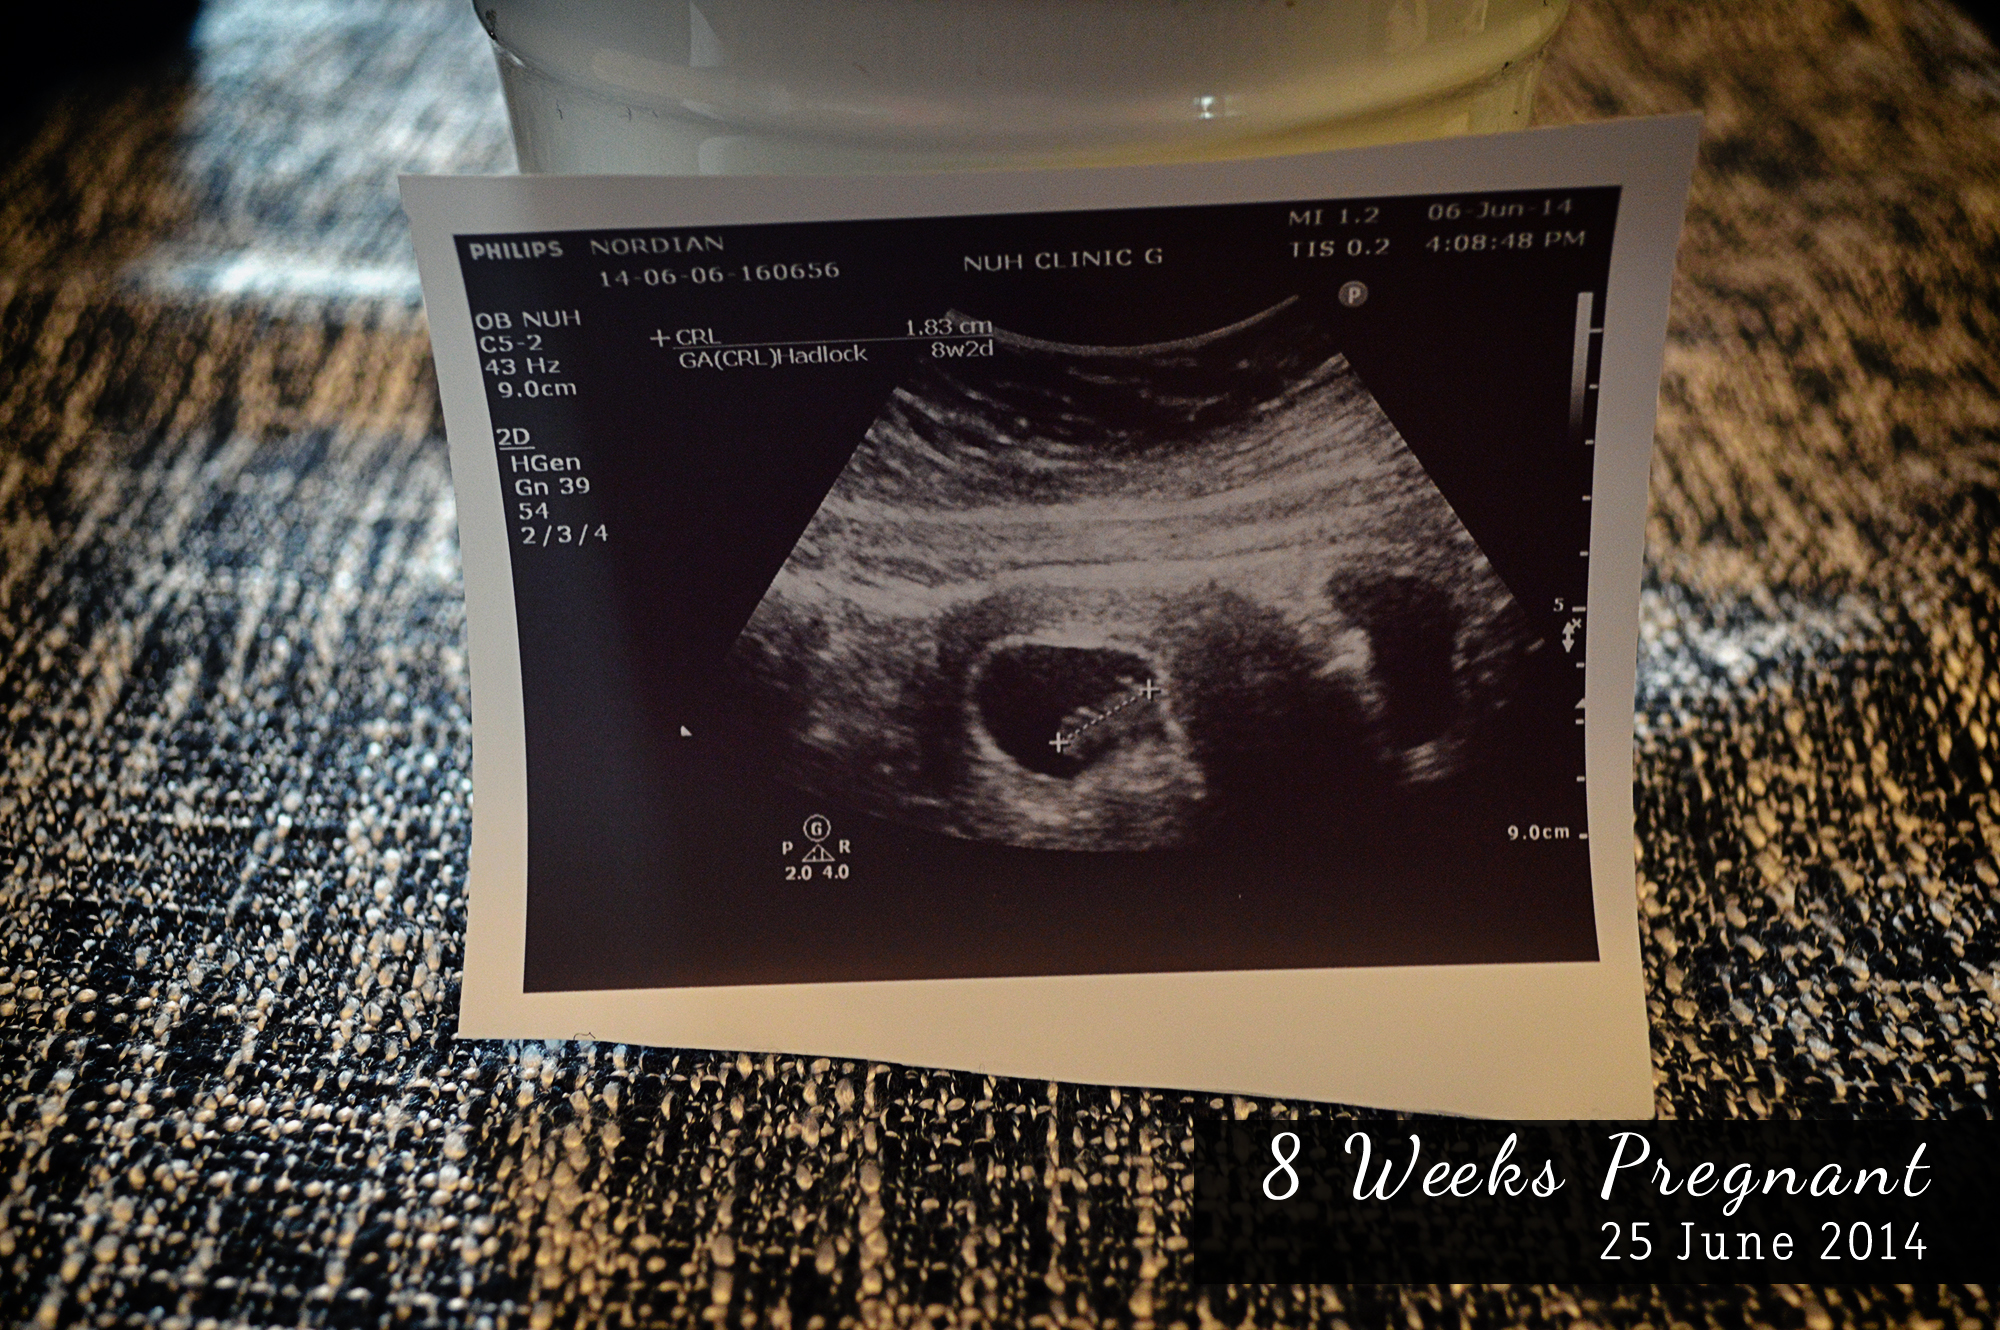

I was compiling all my Ultrasound scan pictures earlier and was amazed at how fast baby is growing.

8 Weeks

and then it tripled up in size in 2 weeks.